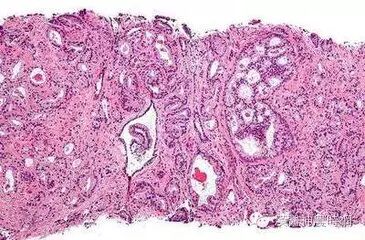

雄激素是对附睾结构,功能影响最大的激素。附睾液中雄激素含量很高,其主要来源于睾网液和血循环。此外一些研究认为附睾上皮也能合成和分泌雄激素,因为实验证明附睾上皮中有LH受体和5α还原酶等一些雄激素代谢有关的酶mRNA的表达。附睾液中的雄激素主要是睾酮和DHT,它们在附睾体部含量最高,与精子的成熟有关。

雄激素的主要作用是促进男性生殖器官的形成和第二性征的发育。睾酮与FSH一起促进睾丸曲细精管的发育和精子发生和成熟。睾酮也是附睾、输精管、精囊和前列腺等的发育和成熟所必需的。睾酮进入前列腺后,经5a-还原酶的作用生成活性更强的双氢睾酮。大剂量睾酮使体内睾酮过量,通过反馈机理,首先抑制下丘脑及腺垂体促性腺激素分泌,继而抑制睾丸内雄激素的合成和精子发生。在女性,雄激素与雌激素配合决定体毛、腋毛和阴毛的分布。在卵巢局部产生的雄激素,转变为雌激素后才发挥生理作用。

5、促进精子的生成:精子是在睾丸中的曲细精管内产生的。据研究,曲细精管中的睾酮浓度要比血液中高100倍,它们以蛋白质结合的形式保留在管内并发挥作用。所以睾酮浓度低的,生精功能就会显着减退。